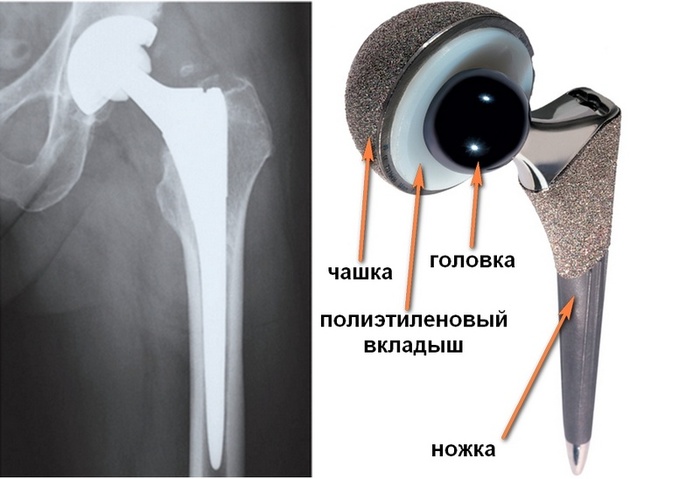

Эндопротез сустава - это искусственный заменитель биологического сустава. В случае с тазобедренным суставом хирург удаляет головку бедренной кости, заменяя ее на искусственную и ставит ответную часть (чашку) в вертлужную впадину в тазовой кости.

Общий вид протеза. Снизу ножка, сверху чашка. Картинка из интернета

Стандартный эндопротез состоит из:

- ножки;

- головки;

- чашки;

- вкладыша.

Картинка из интернета

Разберем более подробно каждую часть.